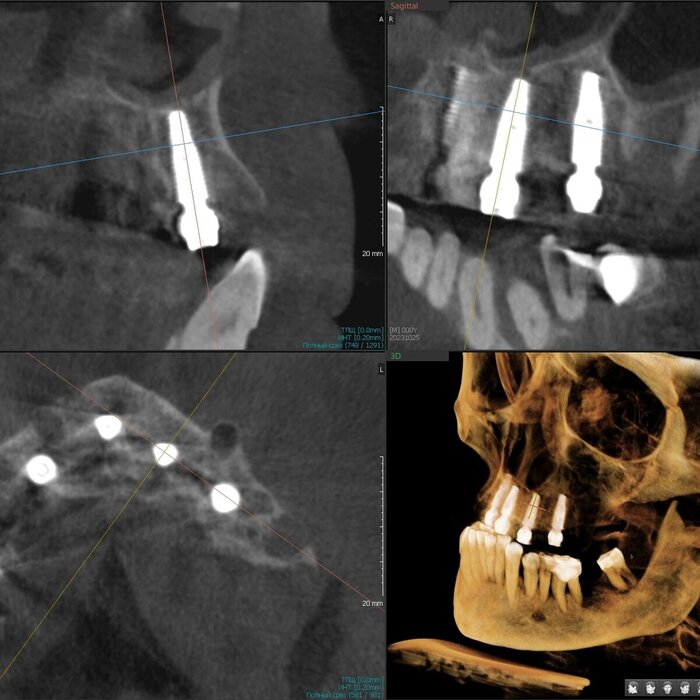

Делаем КЛКТ.

3Д визуализация костей черепа.

Так, мне уже всё понятно - хронический генерализованный пародонтит тяжёлой степени тяжести.

Посмотрим срезы.

Пародонтит.

Зубы цепляются за кость верхушками корней.

Пародонтит.

Куда ни глянь - одна картина.

Пародонтит.

Деструкция кости капитальная.

Пародонтит + периодонтит.

Хуже пародонтита может быть только присоединившийся к нему периодонтит (воспалительный процесс на верхушке корня/корней, в народе "киста") - вот уж где разрушение кости глобальным образом проявляется.

Периодонтит.

Кортикальные пластики утеряны, жаль.